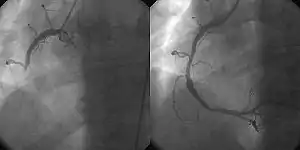

Coronary angiography and angioplasty in acute myocardial infarction (left: RCA closed, right: RCA successfully dilated)